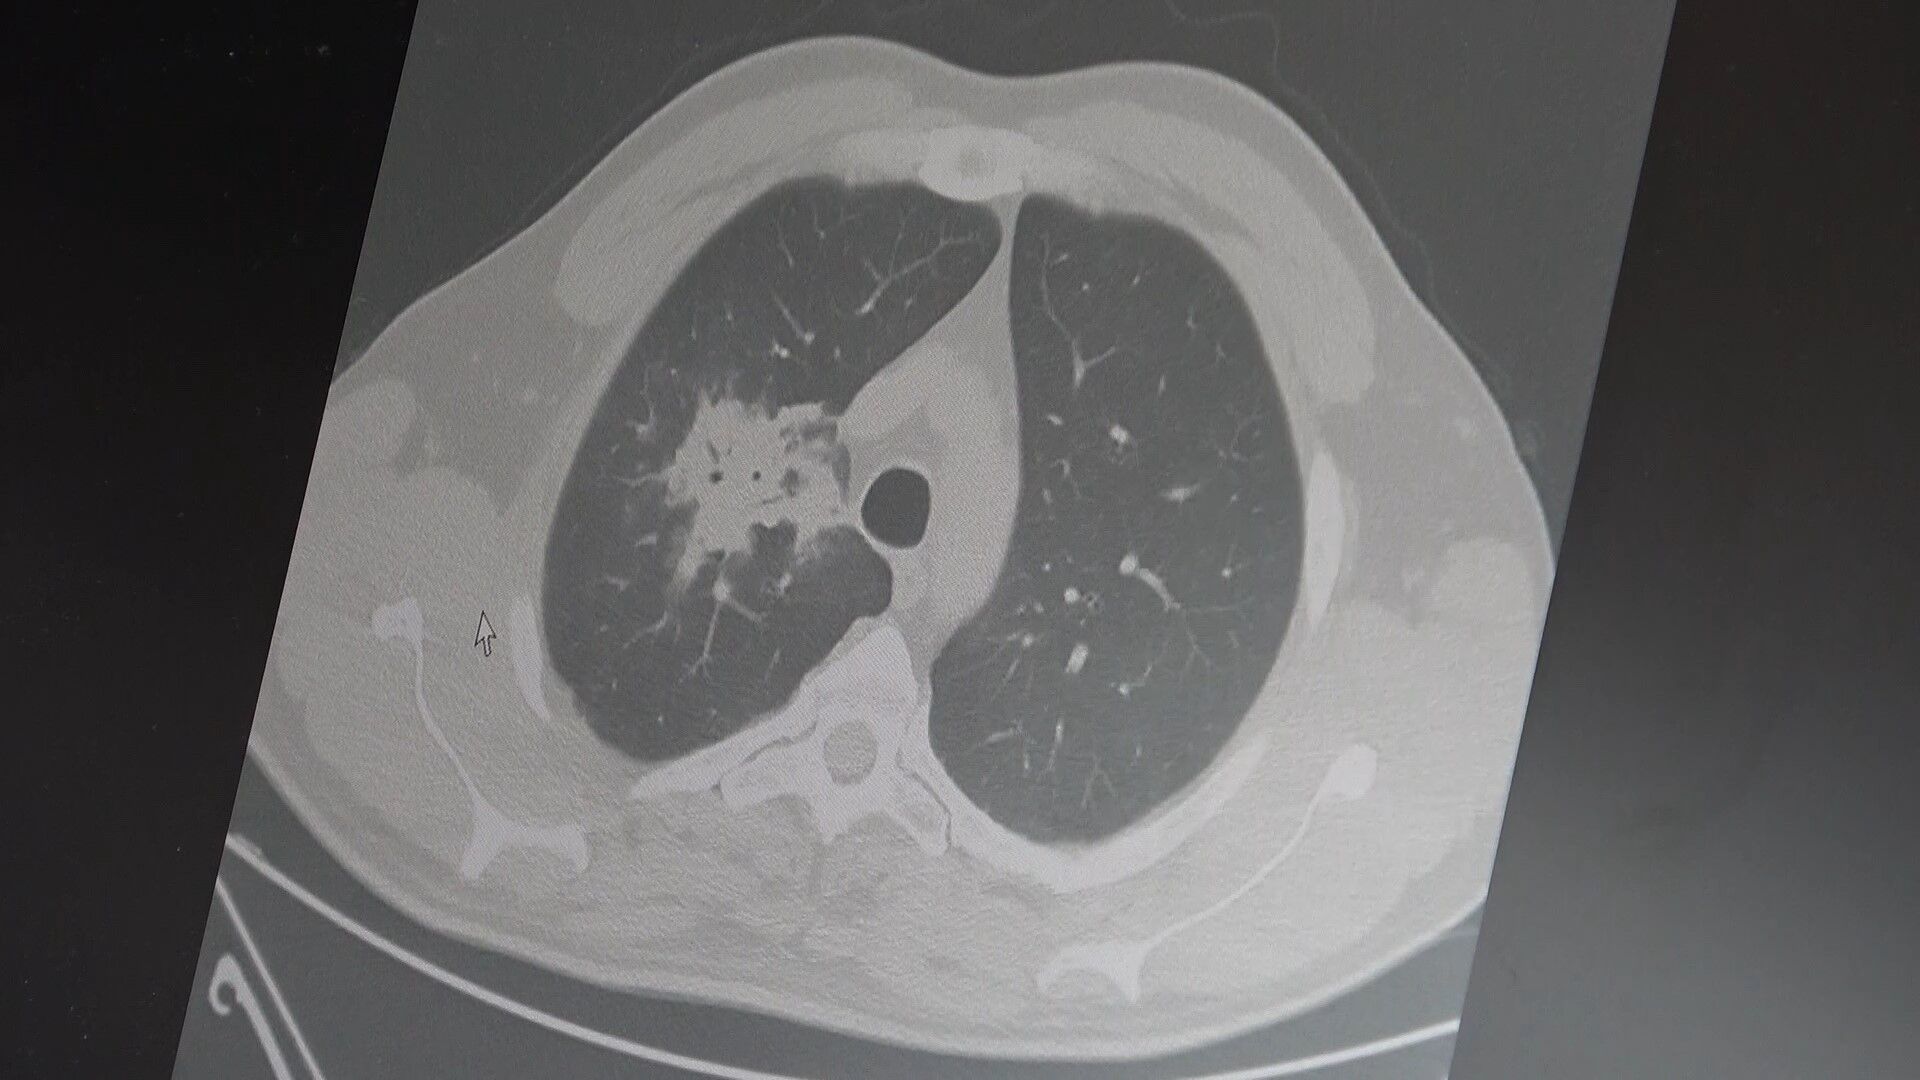

100'den fazla bilimsel çalışmanın incelendiği kapsamlı analizlere dikkat çeken Özkaya, elektronik sigaraların özellikle temas ettiği akciğer ve ağız bölgelerinde kanser riskini artırabileceğine dair güçlü bulgular bulunduğunu aktardı. Uzun vadeli sonuçların henüz tam olarak ortaya çıkmadığını ancak erken uyarı işaretlerinin ciddi olduğunun altını çizdi. Araştırmalarda insan, hayvan ve laboratuvar verilerinin birlikte değerlendirildiğini aktaran Özkaya, elektronik sigaraların içerdiği kimyasalların hücre düzeyinde zarara yol açtığının ortaya konulduğunu dile getirdi.

2024 yılında yayımlanan bir çalışmaya da değinen Özkaya, hem geleneksel sigara hem de elektronik sigara kullanan bireylerde akciğer kanseri riskinin, sadece sigara içenlere göre dört kat daha fazla olduğunun bildirildiğini kaydetti.